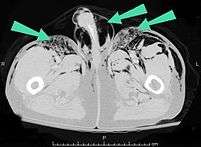

Signs and symptoms of spontaneous subcutaneous emphysema vary based on the cause, but it is often associated with swelling of the neck and chest pain, and may also involve sore throat, neck pain, difficulty swallowing, wheezing and difficulty breathing.[5] Chest X-rays may show air in the mediastinum, the middle of the chest cavity.[5] A significant case of subcutaneous emphysema is easy to detect by touching the overlying skin; it feels like tissue paper or Rice Krispies.[8] Touching the bubbles causes them to move and sometimes make a crackling noise.[9] The air bubbles, which are painless and feel like small nodules to the touch, may burst when the skin above them is palpated.[9] The tissues surrounding SCE are usually swollen. When large amounts of air leak into the tissues, the face can swell considerably.[8] In cases of subcutaneous emphysema around the neck, there may be a feeling of fullness in the neck, and the sound of the voice may change.[10] If SCE is particularly extreme around the neck and chest, the swelling can interfere with breathing. The air can travel to many parts of the body, including the abdomen and limbs, because there are no separations in the fatty tissue in the skin to prevent the air from moving.[11]

Significant cases of subcutaneous emphysema are easy to diagnose because of the characteristic signs of the condition.[1] In some cases, the signs are subtle, making diagnosis more difficult.[13] Medical imaging is used to diagnose the condition or confirm a diagnosis made using clinical signs. On a chest radiograph, subcutaneous emphysema may be seen as radiolucent striations in the pattern expected from the pectoralis major muscle group. Air in the subcutaneous tissues may interfere with radiography of the chest, potentially obscuring serious conditions such as pneumothorax.[19] It can also and reduce the effectiveness of chest ultrasound.[28] On the other hand, since subcutaneous emphysema may become apparent in chest X-rays before a pneumothorax does, its presence may be used to infer that of the latter injury.[13] Subcutaneous emphysema can also be seen in CT scans, with the air pockets appearing as dark areas. CT scanning is so sensitive that it commonly makes it possible to find the exact spot from which air is entering the soft tissues.[13] In 1994, M.T. Macklin and C.C. Macklin published further insights into the pathophysiology of spontaneous Macklin's Syndrome occurring from a severe asthmatic attack.

In severe cases of subcutaneous emphysema, catheters can be placed in the subcutaneous tissue to release the air.[1] Small cuts, or "blow holes", may be made in the skin to release the gas.[16] When subcutaneous emphysema occurs due to pneumothorax, a chest tube is frequently used to control the latter; this eliminates the source of the air entering the subcutaneous space.[2] If the volume of subcutaneous air is increasing, it may be that the chest tube is not removing air rapidly enough, so it may be replaced with a larger one.[8] Suction may also be applied to the tube to remove air faster.[8] The progression of the condition can be monitored by marking the boundaries with a special pencil for marking on skin.[33]